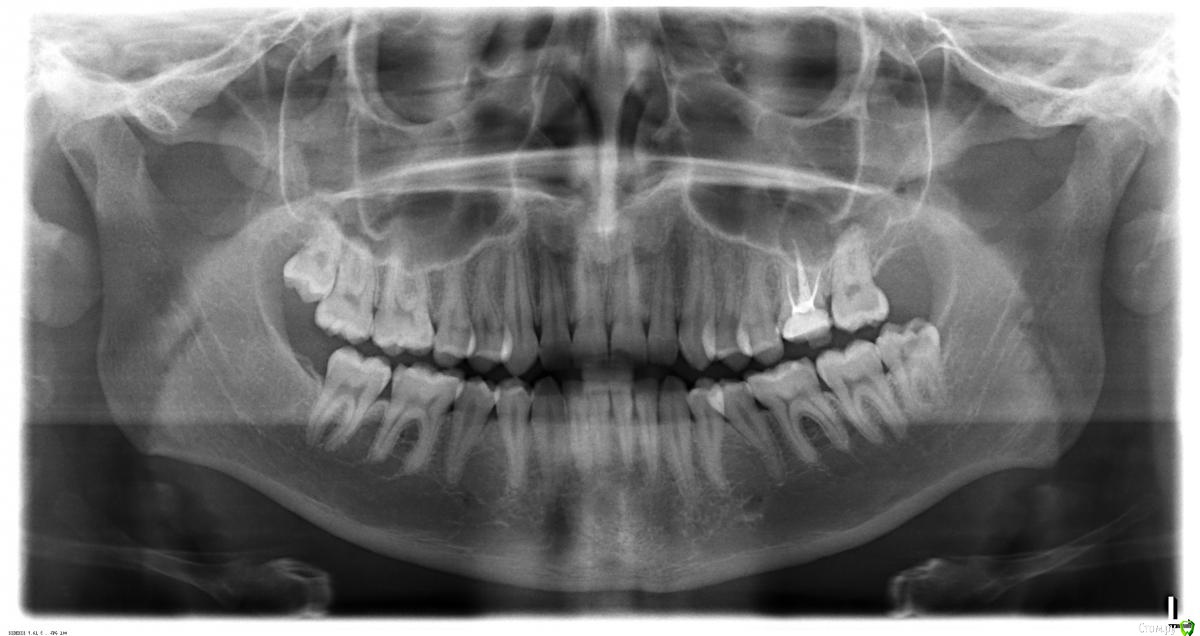

Где-то 3 недели назад эта шестёрка начала разрушаться и в какой-то момент откололся сразу большой кусок зуба. В результате осталось где-то 50% поверхности зуба. Какое-то время из-за этого болела десна, но это прошло довольно быстро. Я пошёл к стоматологам. Был у нескольких, на всякий случай. Сделал снимки (в том числе и 3D, но его я, к сожалению, пока приложить не могу, ибо оставил его дома на диске, выложу как приеду, если будет нужно, 2D снимки прикрепил). По снимкам все врачи нашли что-то плохое под зубом около пазухи (но не доходя до неё, пока, но говорят, что она довольно близко). Говорили разное: либо киста, либо воспаление.

Прикреплено:

1) Панорамный снимок - сделан месяц назад;